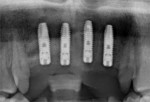

Upon presenting for the implant surgical appointment, the patient reviewed and signed consent forms, and local anesthetic was administered. The surgical guide was tried in to verify its fit on the maxillary dentition adjacent to sites Nos. 7 through 10 (Figure 8 and Figure 9). A flapless approach using tissue punches was utilized. Osteotomies were performed through the surgical guide to accommodate 3.6 mm x 13 mm straight implants (Astra Tech EV) at each of the four sites (Nos. 7 through 10). Cover screws were placed, and a radiograph was recorded to document the implant placement positions (Figure 10). The provisional bridge was reinserted and luted in with temporary cement (TempBond).